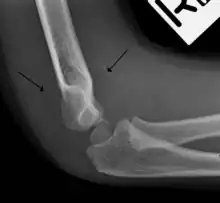

Anterior sail signs as well as posterior fat pad in a child with a supracondylar fracture.

The fat pad sign, also known as the sail sign, is a potential finding on elbow radiography which suggests a fracture of one or more bones at the elbow. It is may indicate an occult fracture that is not directly visible. Its name derives from the fact that it has the shape of a spinnaker (sail).[1] It is caused by displacement of the fat pad around the elbow joint. Both anterior and posterior fat pad signs exist, and both can be found on the same X-ray.

In children, a posterior fat pad sign suggests a condylar fracture of the humerus. In adults it suggests a radial head fracture.

The fat pad sign is invaluable in assessing for the presence of an intra-articular fracture of the elbow. An anterior fat pad is often normal. However a posterior fat pad seen on a lateral x-ray of the elbow is always abnormal. The patient will be unable to flex their elbow and requires orthopaedic input.[2]

The posterior fat pad is normally pressed in the olecranon fossa by the triceps tendon, and hence invisible on lateral radiograph of the elbow.[3] When there is a fracture of the distal humerus, or other pathology involving the elbow joint, inflammation develops around the synovial membrane forcing the fat pad out of its normal physiologic resting place. This is visible as the "posterior fat pad sign" and is often the only visible marker of a fracture, particularly in the pediatrics population.